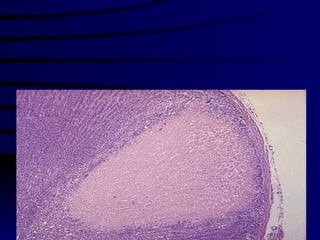

Hepatic congestion Central veins and hepatic sinuses of the centrilobular regions are distended with blood.

Microscopically: nutmeg  liver : Degeneration, atrophy and/or necrosis of the liver cells in the centrilobular regions Fatty degeneration of the liver cells in the peripheral part of the lobules

The central regions of the lobules become red-blue surrounded by a yellow-brown zone of uncongested liver substance. “  Nutmeg  liver”